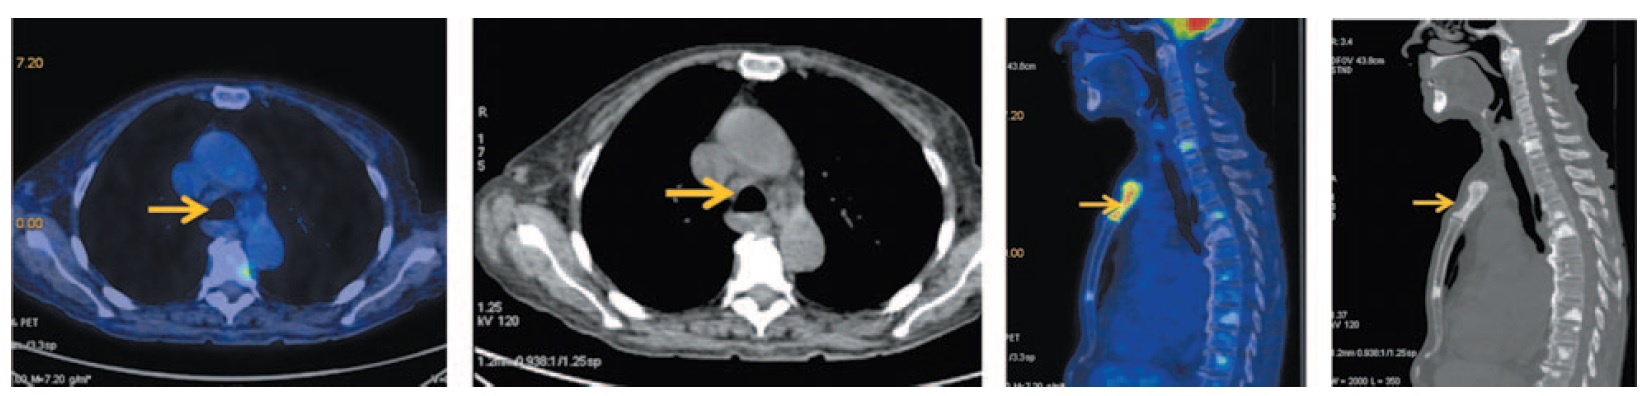

Кроме того, по данным ПЭТ/КТ выявлены множественные медиастинальные лимфатические узлы размером до 15 мм с повышенной фиксацией 18-ФДГ, SUVmax 5,0. Во всех костных структурах отмечается картина смешанной, преимущественно бластической, перестройки, SUVmax 7,65 (рис. 3).

Рис. 3. Больная Б., 72 года, до лечения. На аксиальных и сагиттальных ПЭТ/КТ проекциях определяются множественные медиастинальные лимфоузлы (паратрахеальные верхней и нижней группы, бронхопульмональные с двух сторон, бифуркационные), размером до 15 мм с повышенной фиксацией ФДГ с SUVmax 5,0. Во всех костных структурах зоны сканирования на фоне смешанной перестройки костной ткани (преимущественно бластической, в грудине – литический характер) отмечается очаговый гиперметаболизм ФДГ SUVmax 7,65. / Fig. 3. A 72-year-old woman before the treatment. Axial and sagittal PET/CT images show multiple mediastinal lymph nodes (upper and lower paratracheal, bronchopulmonary on both sides, bifurcation groups of lymph nodes) measuring 15 mm with increased uptake of FDG SUVmax 5.0. In all bone structures of the scanning zone against the background of mixed bone remodeling (mostly blastic lesion, in the sternum – lytic metastatic lesion) with focal increased RFP uptake SUVmax 7.65.